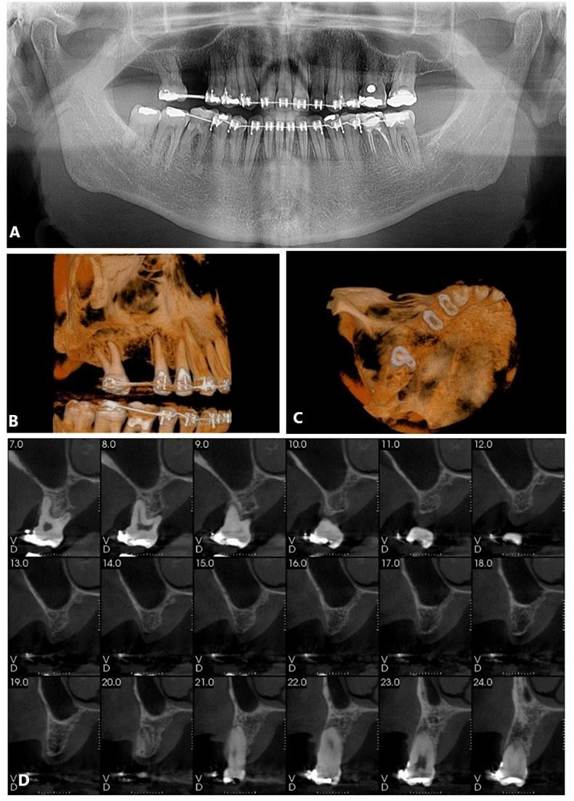

Foram solicitados exames complementares, incluindo radiografia panorâmica e tomografia computadorizada, para avaliação precisa da região anatômica, permitindo a quantificação da espessura e altura óssea (Figura 01. A-D). O plano de tratamento consistiu pela instalação de implantes ultrashort ARCSYS (FGM, Joinvile – SC, Brasil) 4,3 mm x 5,0 mm.

Figura 01. A – D) Exames de imagem complementares evidenciado aspecto inicial da região atrófica na maxila superior direita (área do elemento dental 16).